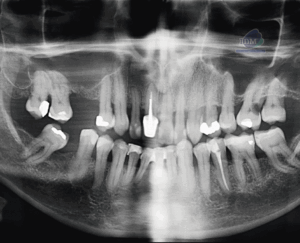

Paciente masculino de 20 años de edad, es referido al Instituto de Diagnóstico Maxilofacial – IDM por dolor en zona mandibular.En la radiografía panorámica (Figura